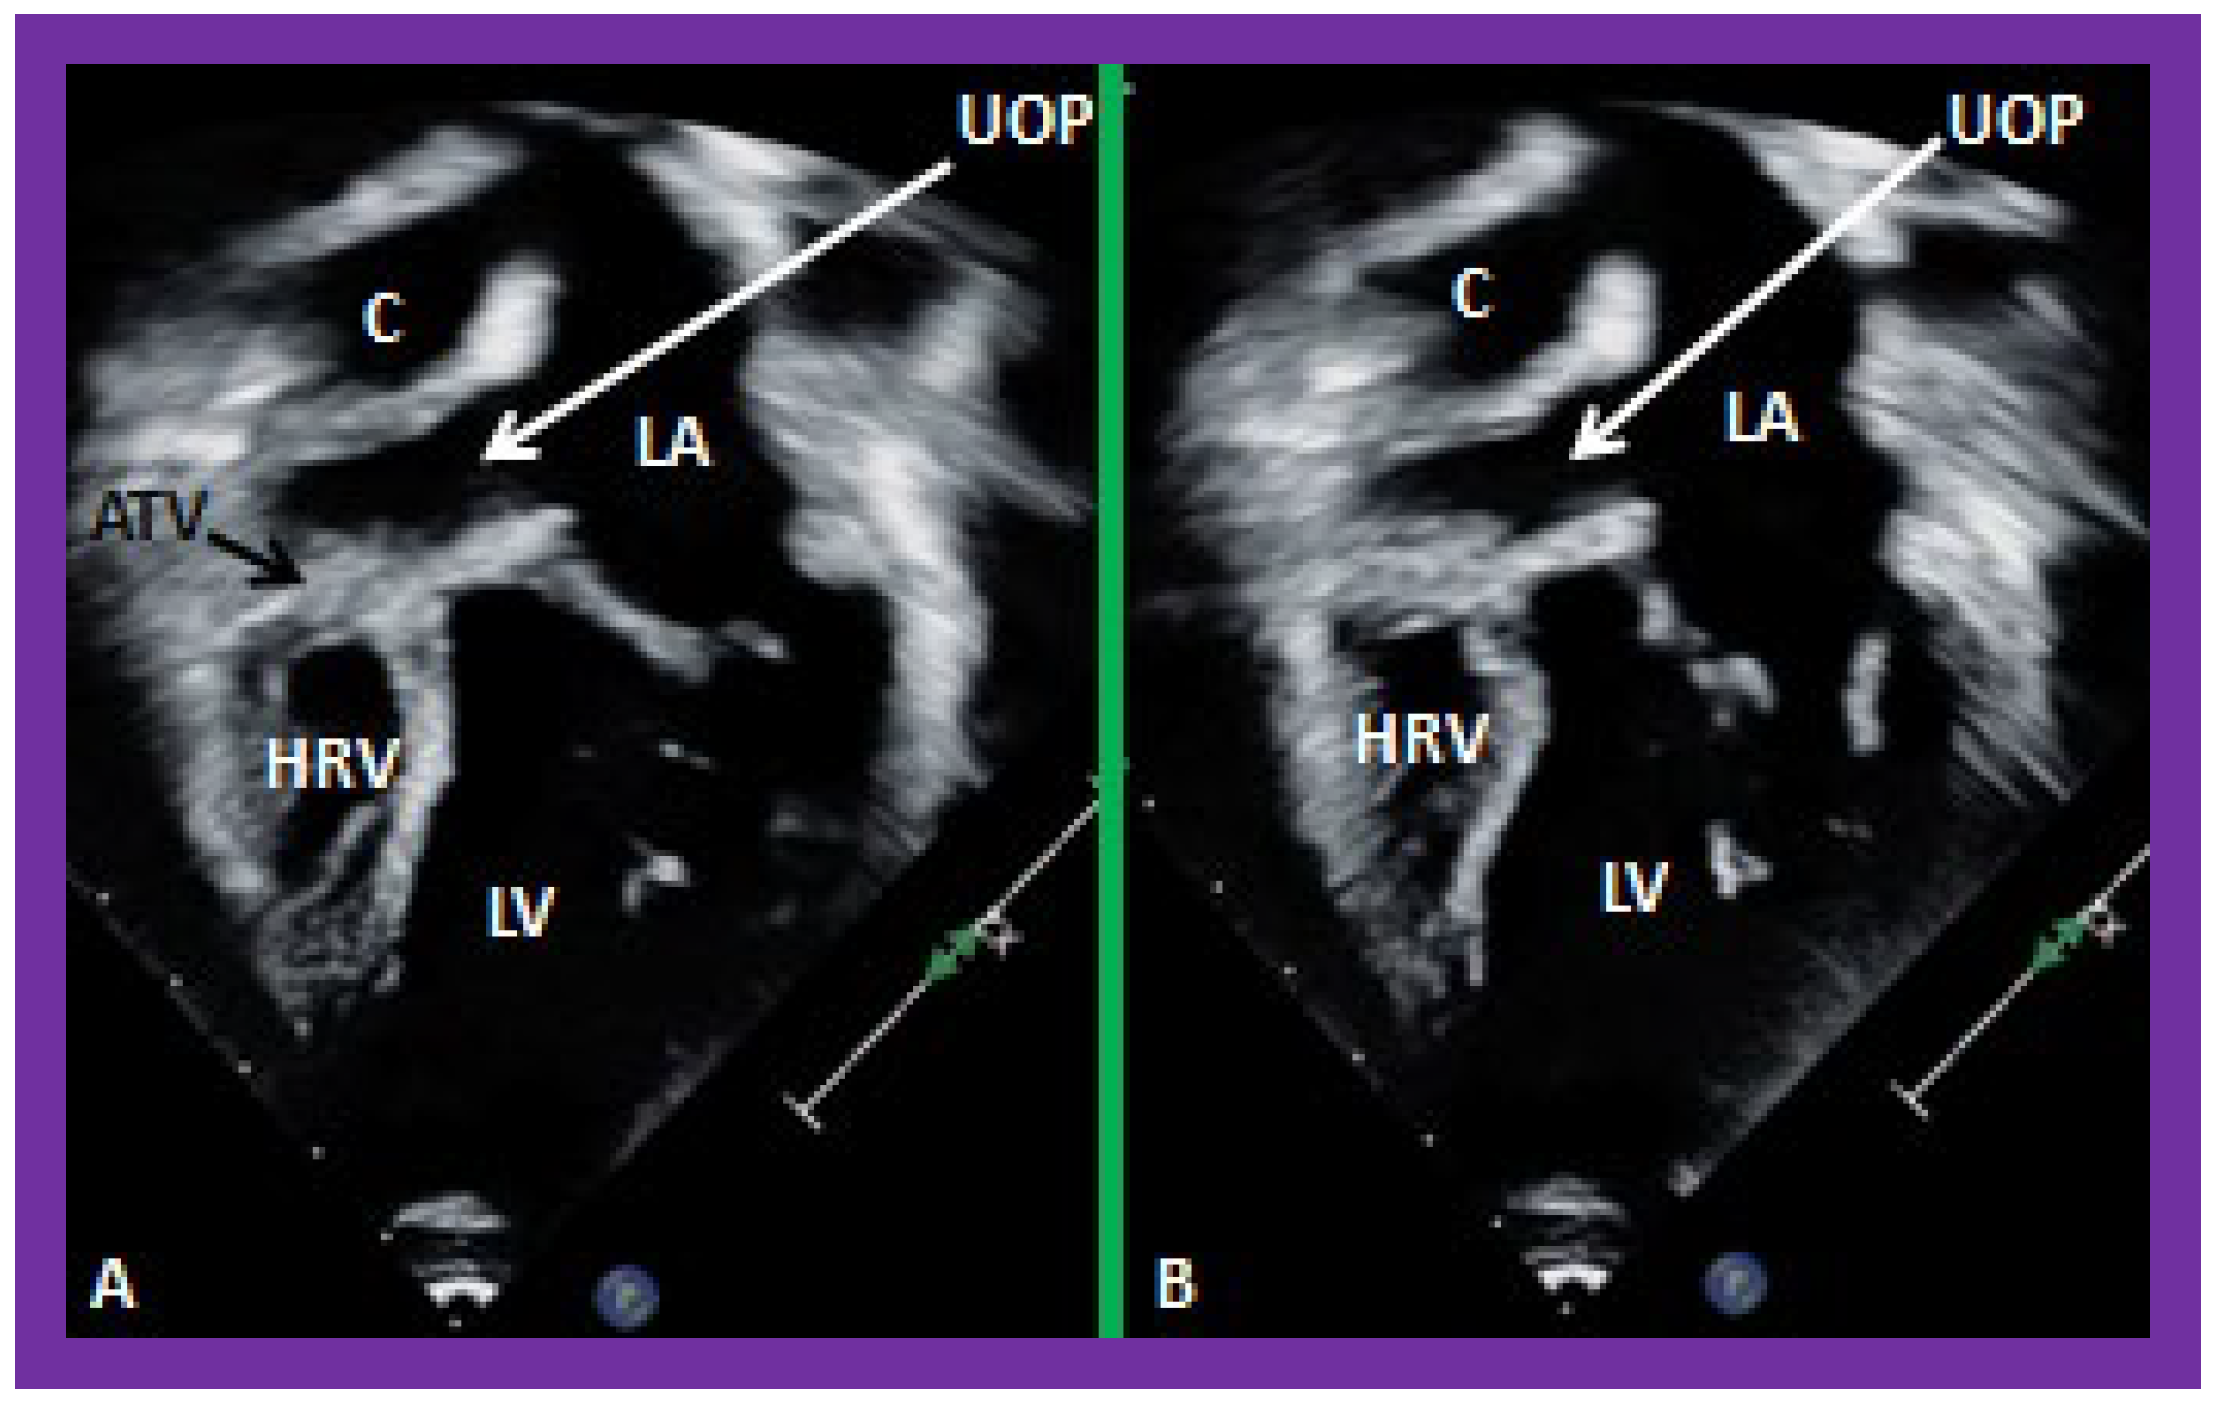

Figure 40. Selected video frames from apical four-chamber views demonstrating unobstructed pathway (UOP) (long arrow) between the right and left (LA) atria; the mitral valve is closed in (A) while it is open in (B). ATV, atretic tricuspid valve; C, conduit; HRV, hypoplastic right ventricle; LV, left ventricle.

Post-Fontan echocardiographic anatomy is best displayed in apical four chamber views, as demonstrated in Figure 38, Figure 39 and Figure 40. The remnants of the RA and the LA are seen (Figure 38, Figure 39 and Figure 40). The remnants of atrial septum are not usually seen since the atrial septum is completely removed either during bidirectional Glenn or Fontan surgery. Unobstructed pathway allowing emptying of blood flow from the coronary sinus and thebesian veins is usually seen in an apical four chamber view (Figure 40).

The LA is usually normal in size (Figure 38, Figure 39 and Figure 40) and empties into the LV; laminar flow across the mitral valve (Figure 41A) can be seen. Drainage of all four pulmonary veins into the LA may be demonstrated by color flow mapping in multiple echocardiographic views. The LV is either normal in size or slightly dilated. In type I patients with normally related great arteries, the LV outflow into the aorta is demonstrable on echo-Doppler with laminar, unobstructed flow with near normal (~1.0 m/s) Doppler flow velocity (Figure 41B and Figure 42). The RV is small and hypoplastic (Figure 39 and Figure 40). If the VSD has already spontaneously closed (Figure 40), the RV has no communication with any other structures since the connection with the PAs has been severed during bidirectional Glenn or Fontan procedures. If the VSD did not undergo spontaneous closure, the RV forms a cul-de-sac connection with the LV (Figure 39 and Figure 43). In Type I patients with atresia of both tricuspid and pulmonary valves (Type Ia), the hypertrophied RV may protrude into the LV outflow region (Figure 44). However, there is usually no evidence for obstruction across this region (Figure 45).